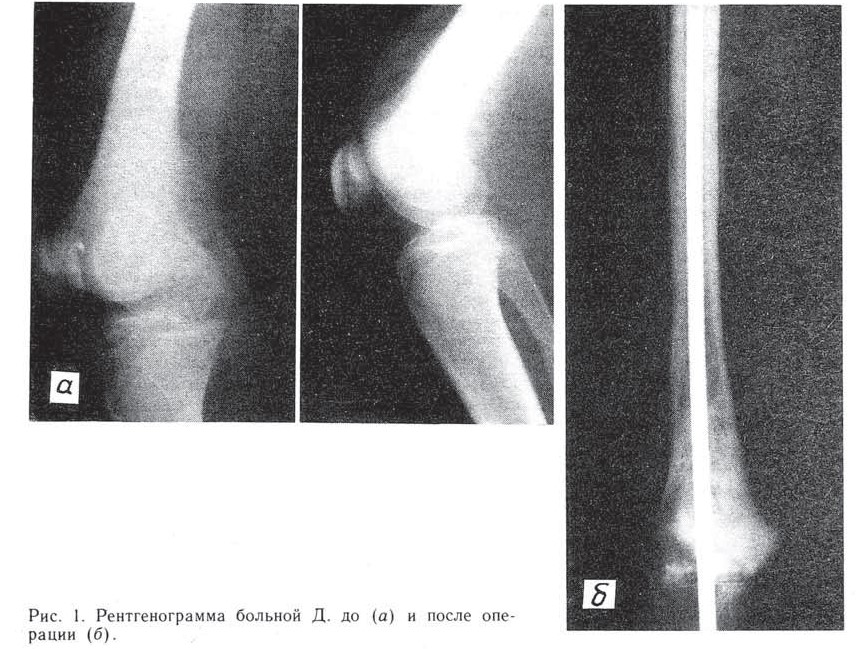

Больная Д., 17 лет, оперирована 12.05.69 по поводу остеогенной саркомы дистального метаэпифиза правой бедренной кости. Произведены резекция дистального суставного конца бедренной кости, кипячение его в течение часа и реплантация с использованием массивного интрамедуллярного фиксатора типа НИИХАИ (рис. 1). Через 3 года возник перелом фиксатора и трансплантата (рис. 2, а), в связи с чем больная вновь оперирована: произведены удаление сломавшегося фиксатора и повторный интрамедуллярный остеосинтез (рис. 2, б). Постепенно произошла перестройка трансплантата, консолидация его на уровне перелома с большеберцовой костью. Больная вскоре вышла замуж и (вопреки нашим советам) родила двоих детей. Резкие гормональные перепады, связанные с беременностями и родами, не обострили течение заболевания. Через 24 года после операции здорова. Старшему сыну 20 лет.

Рис.2 Рентгенограммы той же больной через 3 года после операции.

а — перелом трансплантата и интрамедуллярного металлического фиксатора;

б — сломанный фиксатор удален, произведен повторный интрамедуллярный

остеосинтез.